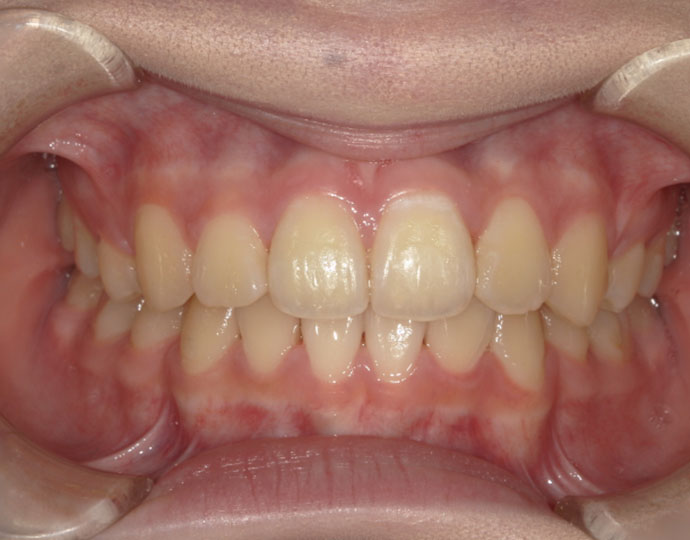

治療後

| 診断 | 叢生歯列不正咬合 |

| 治療方針 | 上下顎左右第一小臼歯の抜歯(計4歯) |

| 治療に使用した装置 | セルフライゲーションブラケット(インタラクティブタイプ) |

| 治療期間 | 2年2カ月 |